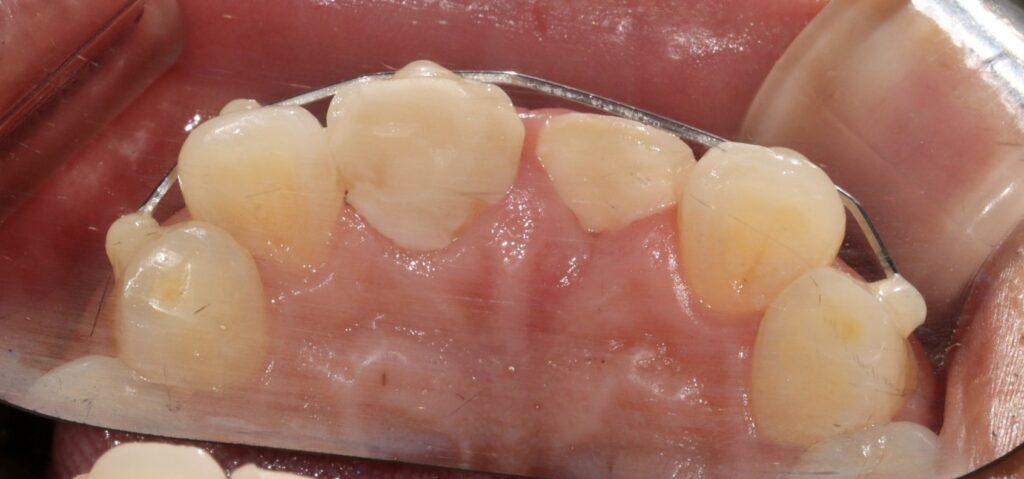

2025.02.12

이후 부러진 뼈가 치유될 수 있게

잠간고정술로 고정하여

치유를 도와줍니다.

치유를 되는 동안

임시치아를 제작하여

생활에 불편함이 없도록

도와줍니다.

치은 연하로 치근까지 파절되어

페룰 확보가 안되기에

교정적 정출을 시켜

자연치를 보존하는 것이 좋아보입니다.

교정적 정출이 필요한 경우

치근 파절이나 잇몸 아래까지

파절된 경우에 시행하는 치료입니다.

건강한 치질을 확보하기 위해

이를 위로 이동시키는 방법입니다.

파절 부위가 잇몸 위로 노출되게 하여

보존적 수복을 가능하게 만듭니다.

치관-치근 비율이 양호하고

치주 상태가 좋을 때 적용됩니다.

치아 보존 의지가 있는 경우

우선적으로 고려되는 치료법입니다.

교정적 정출은 보통 2개월 정도

시간이 소요됩니다.

정출 과정에서 치주조직도

부분적으로 함께 이동됩니다.